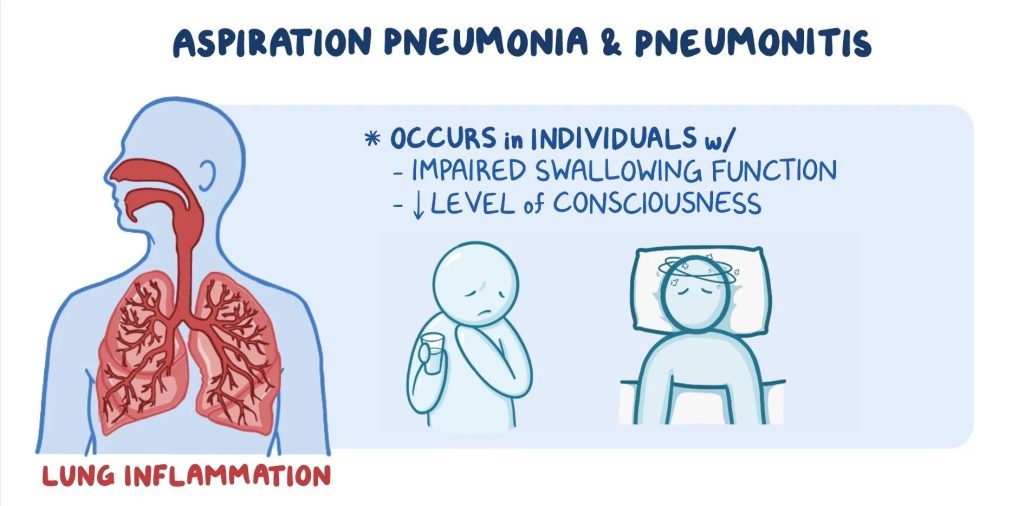

Aspiration Pneumonia is a type of pneumonia that results from inhaling foreign substances into the lungs, which can lead to bacterial infection. The condition is often linked to conditions that impair swallowing or the protective reflexes of the airway. Aspiration can occur during eating, drinking, vomiting, or even while lying down, particularly in those with certain medical conditions.

- Swallowing difficulties: Conditions that impair the swallowing mechanism, such as stroke, neurological disorders, or aging, increase the risk of aspiration pneumonia.

- Neurological conditions: Strokes, Parkinson’s disease, and other neurological conditions can impair the swallowing reflex, leading to an increased risk of aspiration.

- Aging: Older adults are more likely to have swallowing difficulties, and their immune systems may be less effective at combating infections.

- Alcohol use: Heavy drinking or alcoholism can impair the gag reflex and increase the risk of aspiration.

- Sedation: Sedative medications can dull the body’s natural protective reflexes, increasing the likelihood of aspiration.